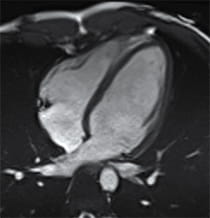

Image of a heart with hypertrophic cardiomyopathy.

- Cardiac MRI – A contrast agent is used with a magnet and radio waves to create an image of your heart. This imaging can better show your provider how thick your heart is and if there is any fibrosis or scarring that has occurred. This information can better guide your treatment plan.